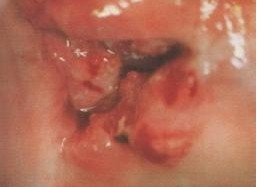

宫颈湿疣是由人乳头瘤病毒(HPV)引起的性传播疾病。宫颈湿疣初期为粟粒大,柔软,淡红色疣状丘疹,逐渐增大,表面凹凸不平显示乳头状、蕈状或菜花状,可有蒂。

宫颈湿疣是由人乳头瘤病毒(HPV)感染引起,并通过性接触而传染,好发于年轻妇女。宫颈湿疣的症状常常会表现为初起为少数淡红色柔软细小丘疹,以后逐渐增大增多,倾向融合或互相重叠,表面凹凸不平呈疣状。